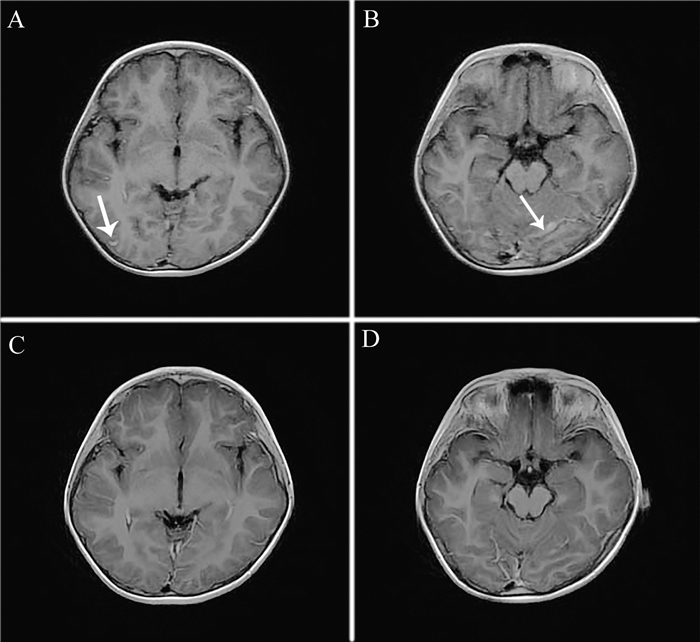

2. 实验室及辅助检查入院后查血常规:白细胞12.24×109/L,中性粒细胞绝对值9.34×109/L,淋巴细胞绝对值1.74×109/L。血清降钙素原小于0.02 ng/ml,CRP 0.2 mg/L,ESR 12 mm/h。血涂片、肝功能、血液生化、心肌酶谱、凝血功能、术前筛查8项、尿常规、大便常规均未见异常。真菌D-葡聚糖、结核T-SPOT均阴性。胸部X线片:双肺纹理稍增多。脑脊液压力大于320 mm H2O (1 mm H2O=0.098 kPa);脑脊液常规:无色透明,微浑,球蛋白定性(+),薄膜无,白细胞数1 514×106/L,中性粒细胞50%;脑脊液生化:蛋白1.03 g/L,糖1.46 mmol/L,氯118.8 mmol/L;脑脊液涂片及培养均未见一般细菌、真菌、厌氧菌、结核杆菌;脑脊液单纯疱疹病毒抗体、自身免疫性脑炎抗体均阴性。头颅MRI平扫+增强:①考虑脑膜炎;②头颅磁共振血管成像(MRA)、磁共振静脉成像(MRV)未见明显异常(图 1A、B)。脑电图:慢波活动增多,界限性脑电图。7月21日回报血清脑囊虫抗体阳性。骨髓涂片提示反应性嗜酸性粒细胞增多骨髓象。根据患儿头痛、发热,颈抵抗,脑脊液检查及头颅影像学检查结果,诊断细菌性脑膜炎。

图 1 一例广州管圆线虫病患儿头颅MRI增强扫描所示病灶影像 A:治疗前,右枕部脑膜可见小片状强化(箭头所示);B:治疗前,左侧小脑幕脑膜可见小片状强化(箭头所示);C:治疗后,原右枕部脑膜强化基本消失;D:治疗后,左侧小脑幕脑膜小片状强化较前减轻 |

入院后予20%甘露醇脱水降颅压,先后予美罗培南(美平)、万古霉素(稳可信)抗感染,患儿热退、头痛缓解,仍易激惹,多次查血常规提示嗜酸性粒细胞计数偏高,脑脊液白细胞及蛋白偏高,遂改用头孢曲松钠(罗氏芬)抗感染。期间行脑脊液常规复查同时送细胞学迈格吉染色,显示脑脊液嗜酸细胞比例多次增高(>60%),提示嗜酸细胞性脑膜炎,结合外周血嗜酸细胞增高,高度怀疑广州管圆线虫感染。8月1日回报送检脑脊液及血清中广州管圆线虫抗体阳性;分子基因检测提示脑脊液广州管圆线虫特异序列数758,置信度高。广州管圆线虫病诊断明确,眼科检查未见异常,遂于8月2日起停用抗生素,予口服阿苯达唑0.2 g、2次/日驱虫,同时予醋酸泼尼松(强的松) 5 mg、2次/日预防虫体死亡后裂解产物引起机体过敏反应。经上述药物治疗2周,患儿无头痛、发热,情绪激惹消失,检查合作。复查脑脊液及血常规示嗜酸性粒细胞计数恢复正常(表 1),9月20日复查头颅MRI增强扫描提示左侧小脑幕脑膜可见小片状强化,较前减轻,原右枕部脑膜强化基本消失(图 1C、D)。